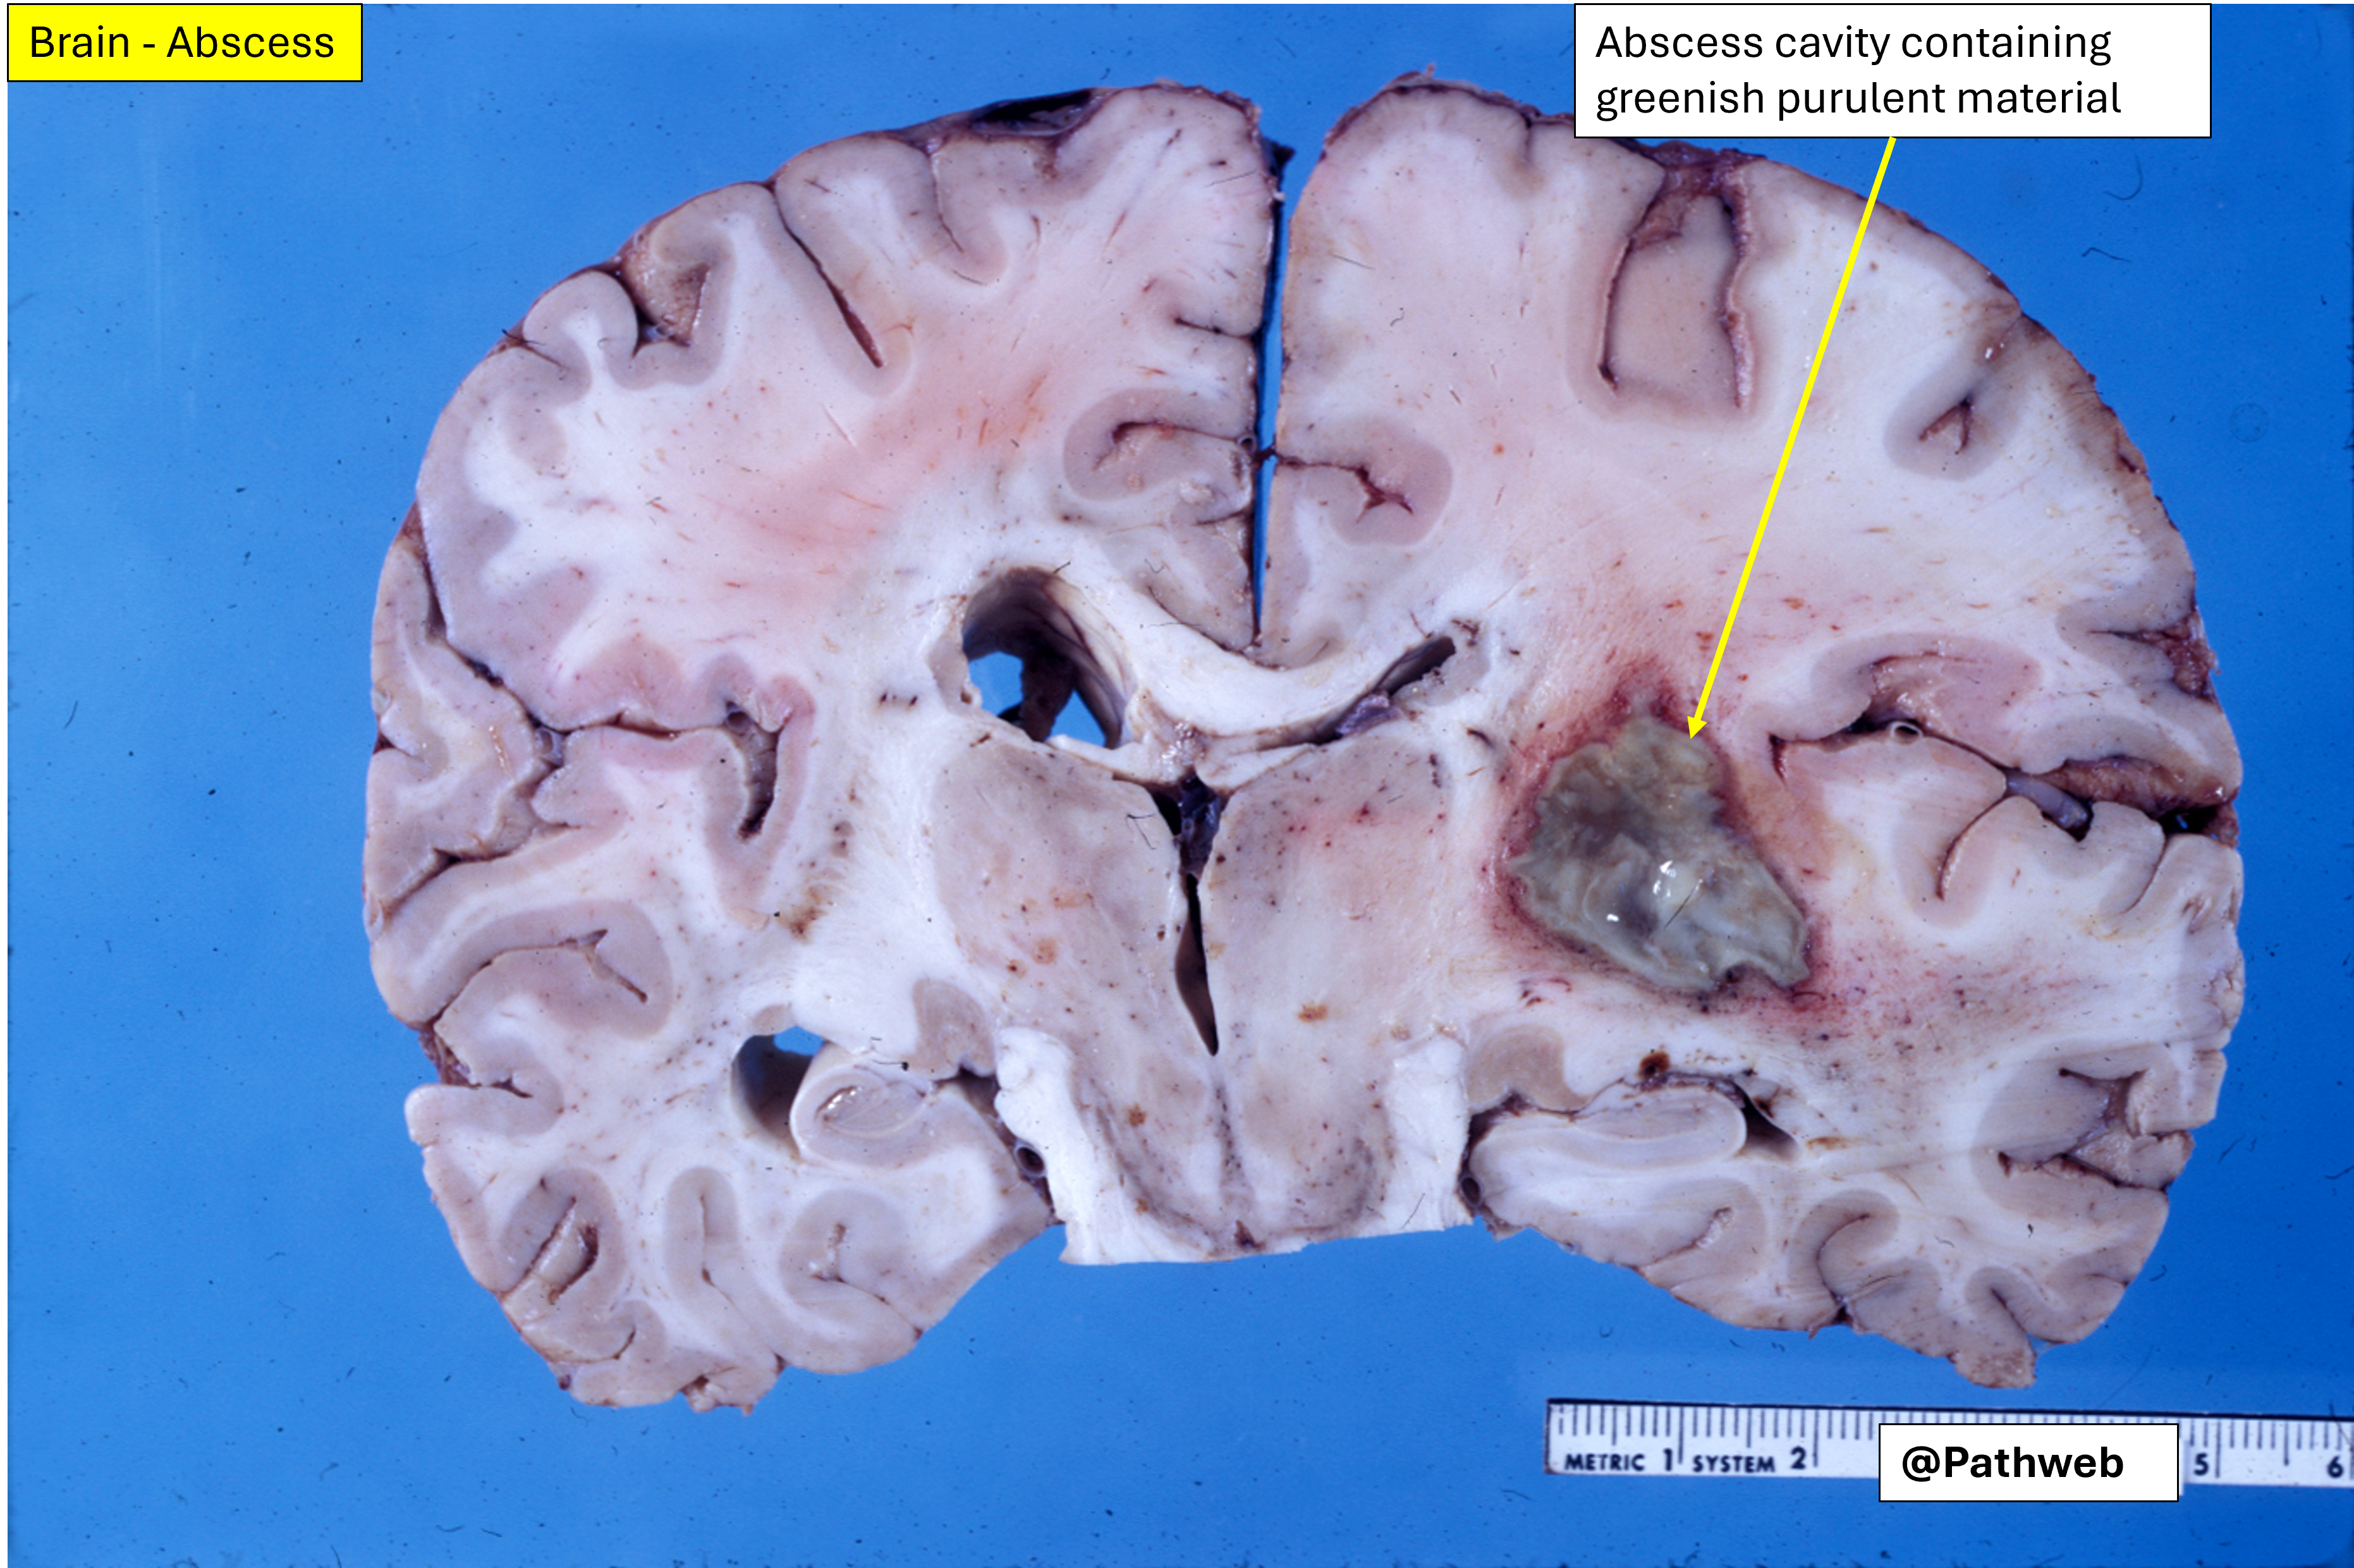

45 year old man with focal neurologic deficits, headache and fever for several weeks.

Cerebrospinal fluid (CSF) analysis showed increase in white cell count, elevated protein concentration but normal glucose content.

The affected cerebral hemisphere is swollen. Cut surface shows a large well-defined cavity (due to liquefactive necrosis and suppuration) lined by a layer of creamy fibrinopurulent exudate resting on a collagenous capsule.

There is compression but no rupture into the lateral ventricle.